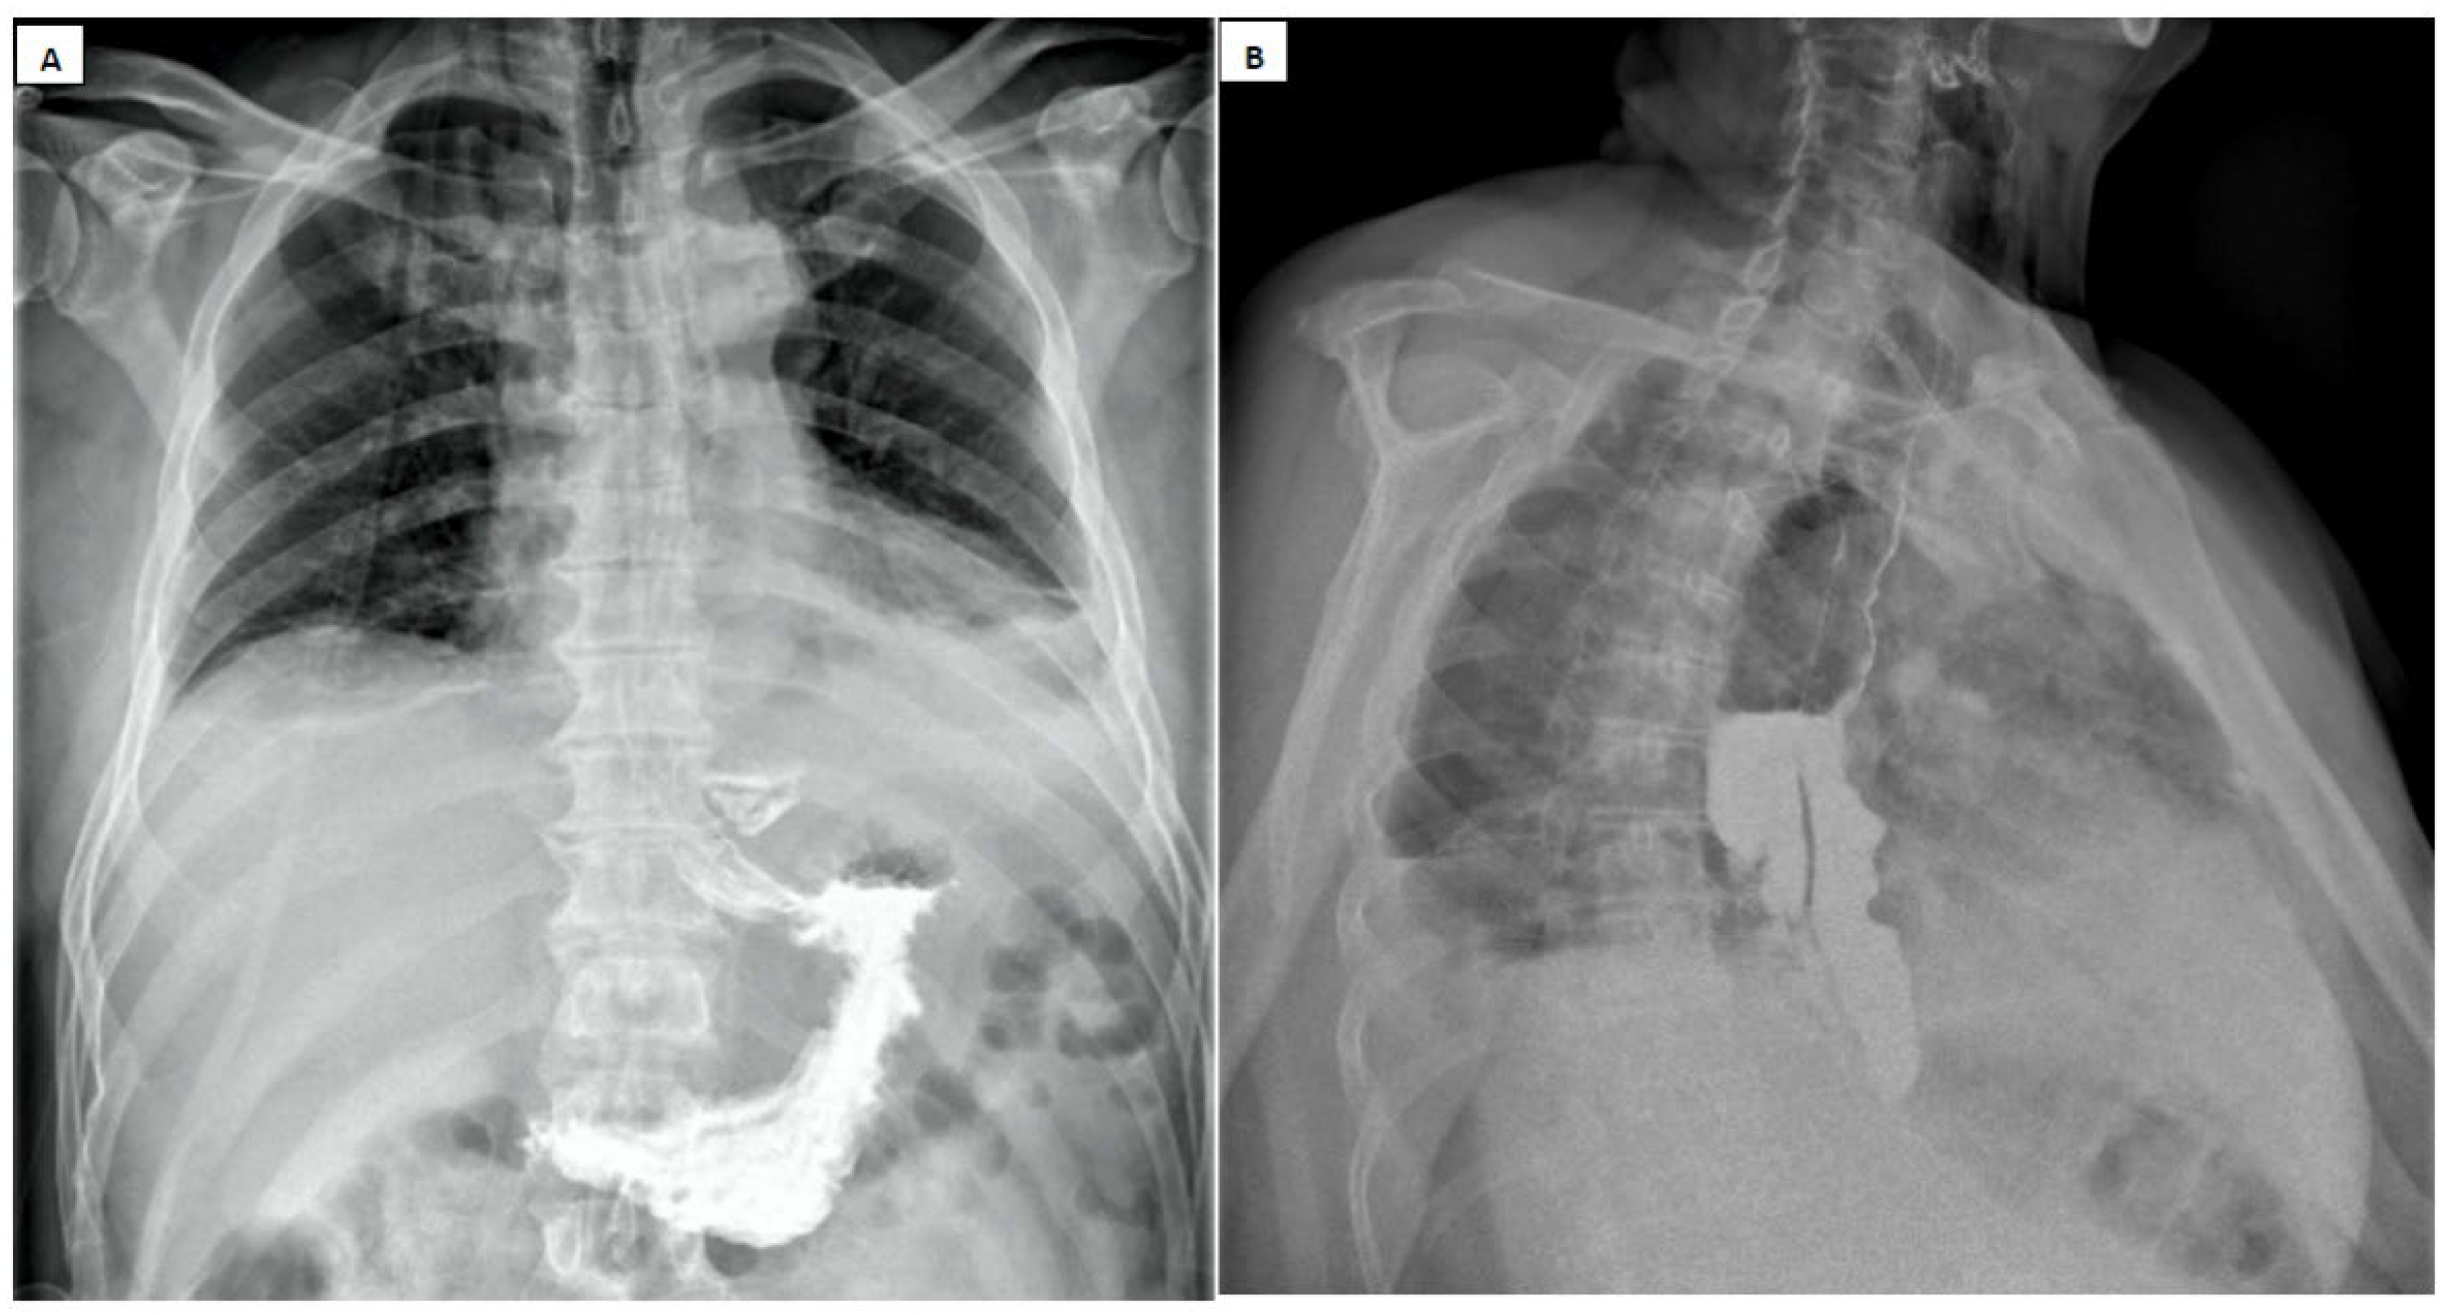

- Pneumomediastinum

- Pneumothorax (especially left-sided)

- Pleural effusion (especially left-sided)

- Air confined to the anterior mediastinum

- Presence of pulmonary emphysema

- Absence of pleural effusion

- Absence of pneumoperitoneum [89].